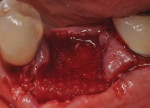

Each socket was treated in one of two manners. If the walls of the socket were determined to be thick and intact, with the diameter not larger than 7 mm to 8 mm, a barrier alone was trimmed to extend 3 mm beyond the socket and placed over the site. If the walls were thinner or if dehiscence or fenestrations were present at the socket, then a bone replacement graft of freeze-dried bone allograft (FDBA) (OraGraft®, LifeNet Health, Inc., www.accesslifenethealth.org) that was hydrated with either sterile water or recombinant platelet-derived growth factor-BB (rh-PDGF-BB) (Osteohealth, www.osteohealth.com) (Figure 2) was placed into the socket and was condensed with light incremental pressure to fill the socket. In two instances a bovine-derived xenograft (BioOss®, Osteohealth) was used mixed with rh-PDGF-BB, as a concurrent internal sinus lift was performed. The polylactic barrier was trimmed to fit the site (Figure 3) so that it also covered the areas where dehiscence or fenestrations were present in the buccal or lingual plate. Flaps were replaced back over the edges of the membrane without purposefully advancing them to achieve primary coverage. The site was sutured with 6-0 expanded polytetrafluoroethylene (ePTFE) (Gore-Tex®, W.L. Gore & Associates, www.gore.com) (Figure 4). For infection control, patients were prescribed amoxicillin 875 mg to be taken twice daily for 7 days, along with topically applying chlorhexidine 0.12% mouthrinse with a cotton swab to the site twice daily for 1 month. If a patient was allergic to amoxicillin, they were prescribed either clindamycin 150 mg four times daily for 7 days, or azithromycin 250 mg with two pills taken on the first day and then one per day for an additional 4 days. Ibuprofen 600 mg or acetominophen with codeine were used for analgesia. Patients were told to refrain from chewing on the site to avoid dislodging the barrier.